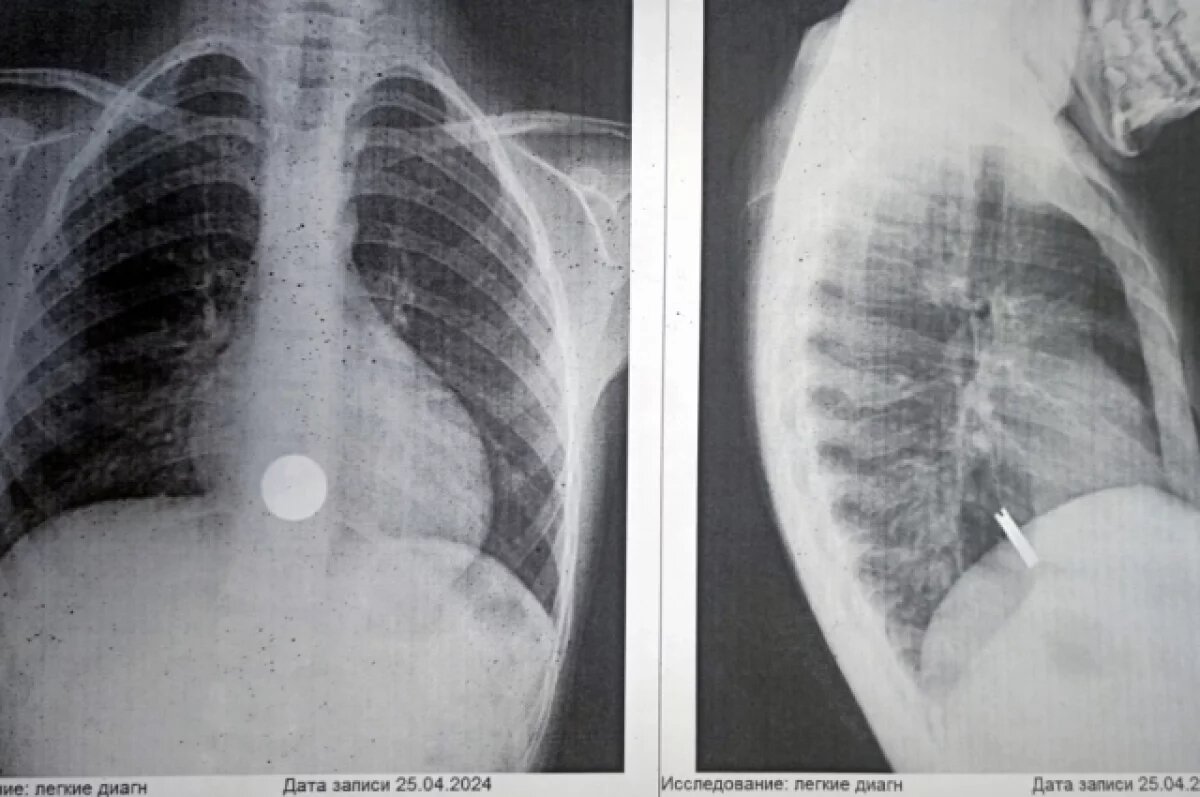

У 7-летнего мальчика при рентгене груди обнаружились инородные тела в пищеводе. Ребенка доставили в больницу для соматического обследования. Оказалось, что в пищеводе у малыша были три 50-копеечные монеты, которые встали друг за другом. При этом мальчик не испытывал боли или затруднений при приеме пищи. Врачи смогли извлечь монеты с помощью методики внутрипросветной эндоскопии.

«Чаще всего инородные тела в пищеводе заканчиваются катастрофой. Каковы последствия? От перфорации в пищеводе, медиастинита (воспаления тканей средней части грудной клетки) до тяжёлых осложнений», - сообщил хирург, эндоскопист ДГКБ №7 Константин Герасименко.